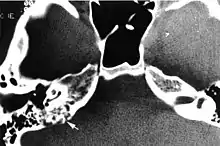

CT in patient with VHL syndrome through the petrous ridge demonstrates bone erosion at the site of the endolymphatic sac tumor, typical of the locally aggressive behavior of this tumor (curved arrow).

Imaging studies help to identify the tumor and the specific anatomic site of involvement. Magnetic resonance images show a hyperintensity (hypervascularity) of a heterogeneous mass by T1 weighted images. Computed tomography shows a multilocular, lytic destructive temporal bone mass, centered on the vestibular aqueduct (between internal auditory canal and sigmoid sinus).[1][6][7]